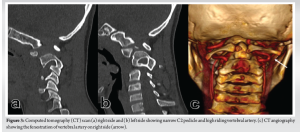

A 14-year-old boy presented to the spine clinic with progressive weakness of the bilateral upper limb, progressing to bilateral lower limb for the past 1.5 years following trivial trauma to the neck and with bowel and bladder incontinence for the past 1 year. At presentation, he was not able to stand without support, had increased tone (modified Ashworth grade 1) in bilateral upper and lower limbs, with functional motor power present and no sensory deficit in any of the dermatomes. On elicitation, both upper and lower limb reflexes were exaggerated. Exaggerated pectoralis reflex and presence of scapulohumeral reflex suggested a clinical diagnosis of supra-axial cervical myelopathy. On further evaluation, special signs such as Hoffman’s sign and grasp-release test were positive. Cervical spine radiograph showed atlantoaxial subluxation with decreased posterior atlanto-dens interval along with fusion of C2 and C3 vertebrae (Fig. 1). On magnetic resonance imaging cervical spine, thecal sac and spinal cord compression at the level of C1/C2 joint with no visible cerebrospinal fluid rim was noted (Fig. 2). 3D Computed tomography angiography (CTA) of the cervical spine showed an incomplete anterior and posterior arch of the atlas with well-corticated bony fragments within the posterior arch defect. Note of fenestration of VA on right side and high-riding VA was also made (Fig. 3). A final diagnosis of supra-axial extradural compressive cervical myelopathy due to congenital atlantoaxial subluxation with anomalous VA (Nurick Grade 5) was made. The patient was planned for C1-C2 reduction and posterior instrumented fusion using C1 lateral mass and C2 laminar screws under intraoperative neuromonitoring. The patient was positioned prone on Mayfield, and a longitudinal midline approach from C1 to C3 was carried out, elevating the paraspinal muscle subperiosteally from the midline. A congenital defect in the posterior arch of C1 was noted. First, the left side C1 lateral mass screw was put after identifying the entry point. On the right side, the aberrant VA was freed from the posterior arch of C1 and retracted, inferiorly exposing the lateral mass of C1 along with facets of C1-C2 joint, and C1 lateral mass screw was inserted. Further, laminar screws were placed bilaterally in C2. C1 was reduced over C2 using rod cantilever mechanism and by applying compression force bilaterally between the C1 lateral mass and the C2 laminar screws. Decompression was achieved by removing the remaining C1 posterior arch and corticated bony fragment from the midline. Harvested local bone autograft was placed in the C1-C2 joint on the left side and the prepared fusion bed posteriorly (Figs. 4 and 5).

The atlantoaxial joint, located between the first and second cervical vertebrae, is a complex joint that allows for a significant range of motion in the neck [5]. Non-traumatic atlantoaxial subluxation can lead to pain, stiffness, deformity, and neurological deficits. The condition can be caused by a variety of factors, including congenital abnormalities, degenerative changes, and inflammatory conditions [6]. In congenital cases, atlantoaxial subluxation may be associated with a VA anomaly, which can further complicate the condition. Any disruption to its flow can lead to serious neurological consequences, including cerebrovascular injuries [7]. Embryonic development of VA can easily explain various variations found at the CVJ [8]. VA variation at the CVJ is of 3 types – persistent first intersegmental artery (FIA), extracranial origin of the posterior inferior cerebellar artery (PICA), and fenestration of the VA [9,10]. The most common is persistent FIA, present in 3.2% of patients. The next is PICA, present in 1.1% of cases. The least common variant is fenestration, present in 0.9% of patients, which was present in the present case. It occurs when there is both a normal VA branch as well as a persistent FIA, which then merge within the spinal canal [11]. VA anomaly with congenital CVJ pathology is a rare but potentially disabling condition that requires prompt diagnosis, thorough evaluation of the abnormal anatomy, and treatment. Surgical management typically involves decompression of the spinal cord and reduction of the joint, and stabilization. There are several surgical techniques that may be used, including posterior fixation, anterior fixation, and combined approaches. The choice of surgical technique depends on various factors, including the location and severity of the subluxation, the presence of other spinal abnormalities, and the patient’s overall health status. Among posterior fixation methods between C1 and C2, C1 lateral mass–C2 pedicle screw fixation is more popular and rigid [12]. These variations in VA may affect screw placement to the C1 lateral mass. Wright et al. reported the incidence of VA injury in CVJ anomalies during screw placement to the rate of 4.1% [13]. Hong et al. have described various methods to minimize this injury by predetermining the entry point [14]. The first technique is to mobilize VA inferiorly together with C2 nerve root before screw placement at the C1 inferior lateral mass, used in the present case lateral mass screw insertion on the right side. Another technique is to use C1-2 trans-articular screw fixation, which could not be used because of the presence of subluxated C1/C2 joint and high riding VA. The third technique is skipping the C1 level and using C0 as the proximal fixation level, as Abtahi et al. did in their case [11]. To save the motion of the C0-C1 joint in the young, we preferred not to use this fixation method. The third method is to choose the superior lateral mass as an alternative starting point. But this required a persistent FIA in which there is complete absence of a VA remnant in the normal position superior to the C1 ring. The last technique they described was to choose the C1 dorsal arch as an entry point, but because of the deficient posterior arch, this technique also could not be used. As the C2 pedicles were very narrow in the sagittal plane and the spinous process height was adequate, translaminar screws were inserted, which have shown equal pull-out strength compared to C2 pedicle screws [15] along with decreased chances of VA injuries in VA anomalies [16]. To the best of our knowledge, this is the first surgical case report addressing these complex bony and vertebral anomalies at the CVJ along with VA anomalies in a single patient, using the C1 lateral mass and C2 laminar screws. Blunt trauma to the neck with a congenital CVJ anomaly may have induced the patient’s symptoms. The ventral and dorsal bony pathology compressed the upper cervical spinal cord. It has been shown that decompression alone in these pathologies may lead to neurological deterioration [17]. Hence, posterior decompression for the spinal cord along with posterior fixation to reduce the atlantoaxial joint was performed in the case. While surgical management of congenital AAS with VA anomaly can be effective, it is not without risks. Complications may include infection, bleeding, nerve injury, and device failure. Pre-operative thorough evaluation and planning of these conditions are crucial for surgical planning. The usefulness of 3D CTA for evaluating VA anomalies at the CVJ has been described in various papers [2]. In addition, we must also pay great heed to subluxation between C1 and C2 in not only the horizontal direction, but also the vertical direction, because vertical dislocation is often missed [18]. The long-term outcomes of surgery for this condition are not well established in the literature, and this report might provide insight into fully understanding the risks and benefits of posterior decompression and C1-C2 screw rod construct even in cases with aberrant bony and VA anomalies.